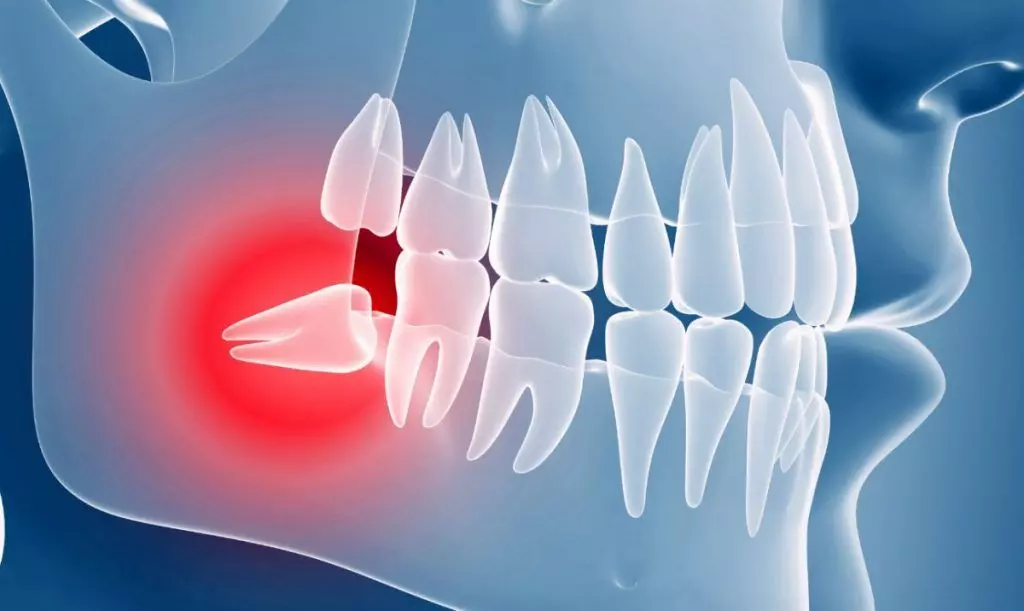

Дентальная галерея: ретинированный зуб клык и его лечение

Раздел: Компас решений